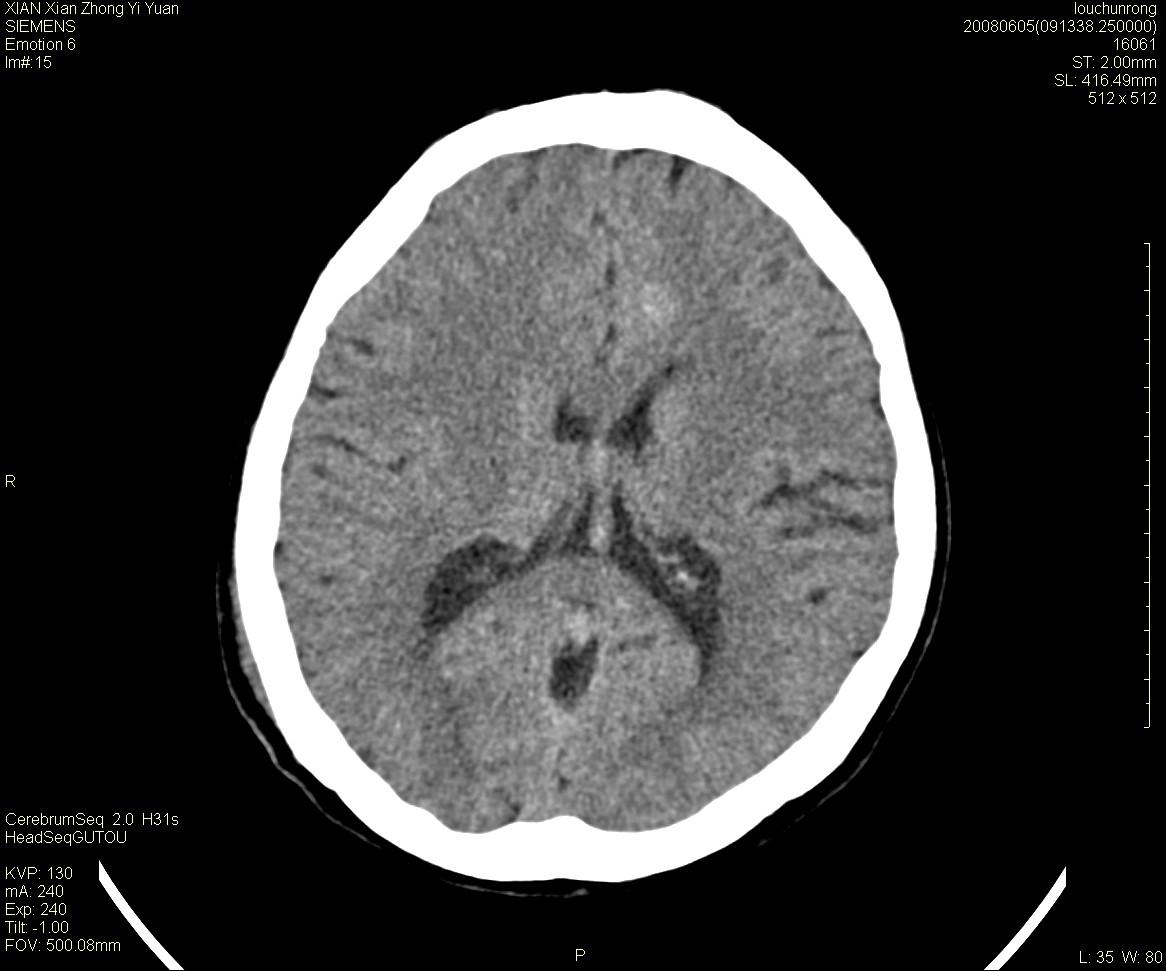

标题: CT13860:F52Y,,头外伤致头晕半天,以前无不适。 [打印本页]

标题: CT13860:F52Y,,头外伤致头晕半天,以前无不适。

层厚2mm。

静脉窦血栓? mri检查

大家看左额叶大脑镰旁高密度影

两侧脑室体部距离增宽,胼胝体发育不良?

中线附近、枕叶近枕骨处及脑内多发点条状强化影,考虑血管异常?

先天发育性疾病

大脑大静脉池内的密度不均,双侧脑室增宽,我看右异常这块。战友们看看

侧脑室前角变形、变窄,考虑侧脑室粘合;余未见明显异常。